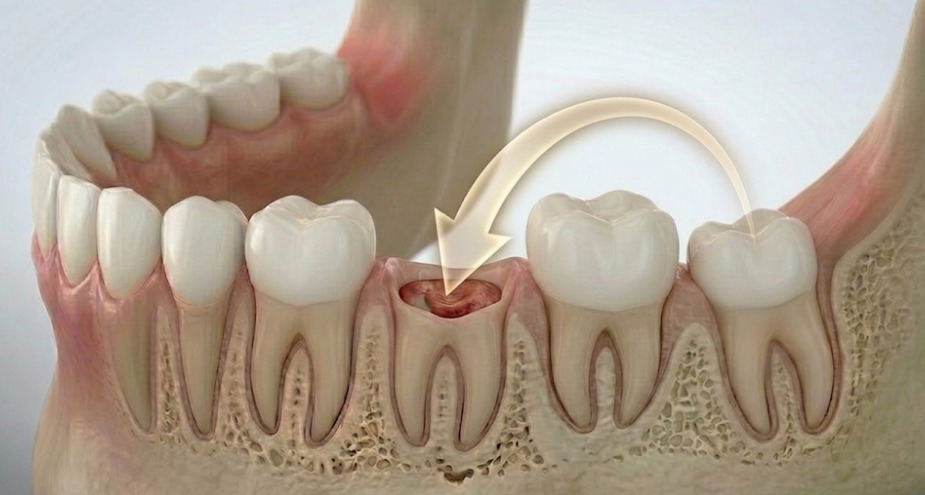

自分の歯を「再利用」する、体に優しい再生治療「自家歯牙移植(歯の移植)」とは、虫歯や破折などで残せなくなった歯の場所に、自分の「親知らず」や「機能していない歯」を移し替える治療法です。 「抜歯後はブリッジやインプラントしかない」と思われがちですが、条件が合えば、ご自身の天然歯をもう一度活用できる可能性があります。

向かって左端で横を向いてはえているのが親知らずを、抜歯せざるを得ない状態の放置された虫歯に移植します。

治療後5年のレントゲンとそのカラー写真です。 この方の反対側の顎の中に埋もれている親知らずを抜歯し、即時移植で治療することができました。